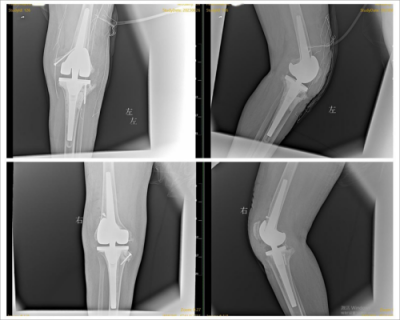

术后患者双膝影像(上两图为左膝、下两图为右膝)